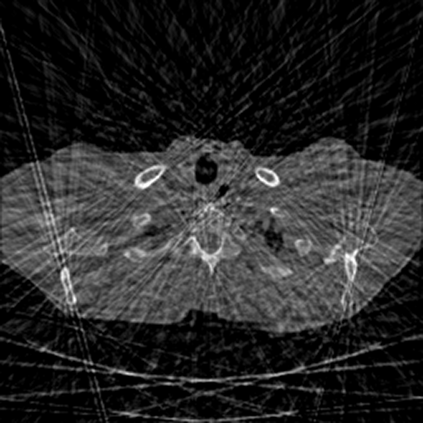

Sparse-view computed tomography (CT) -- using a small number of projections for tomographic reconstruction -- enables much lower radiation dose to patients and accelerated data acquisition. The reconstructed images, however, suffer from strong artifacts, greatly limiting their diagnostic value. Current trends for sparse-view CT turn to the raw data for better information recovery. The resultant dual-domain methods, nonetheless, suffer from secondary artifacts, especially in ultra-sparse view scenarios, and their generalization to other scanners/protocols is greatly limited. A crucial question arises: have the image post-processing methods reached the limit? Our answer is not yet. In this paper, we stick to image post-processing methods due to great flexibility and propose global representation (GloRe) distillation framework for sparse-view CT, termed GloReDi. First, we propose to learn GloRe with Fourier convolution, so each element in GloRe has an image-wide receptive field. Second, unlike methods that only use the full-view images for supervision, we propose to distill GloRe from intermediate-view reconstructed images that are readily available but not explored in previous literature. The success of GloRe distillation is attributed to two key components: representation directional distillation to align the GloRe directions, and band-pass-specific contrastive distillation to gain clinically important details. Extensive experiments demonstrate the superiority of the proposed GloReDi over the state-of-the-art methods, including dual-domain ones. The source code is available at https://github.com/longzilicart/GloReDi.